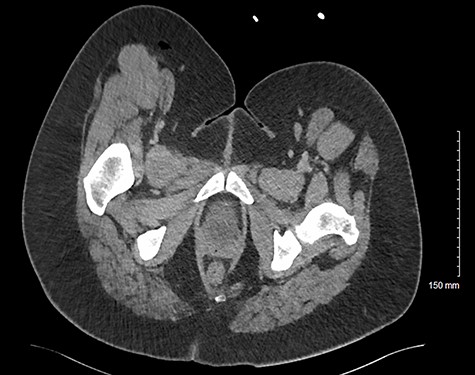

A normally fit and well 33-year-old woman presented to the emergency department with right flank and thigh pain for 3 weeks. She had previously been seen in primary care following 1 week of thigh pain, which was initially attributed to a musculoskeletal cause for which she was advised to take simple analgesia. The patient returned to the emergency department when the pain significantly worsened, and she developed an associated fever. Apart from a high body mass index, she had no other co-morbidities. On examination, she had diffuse erythema and tenderness over her proximal thigh, particularly marked on the medial aspect (Fig. 1). The erythema extended to her ipsilateral iliac crest. There was no palpable fluctuance or crepitus. Pain was exacerbated by movement at the hip joint, but there was no reduction in the range of movement. There was no guarding or tenderness on abdominal examination. At this time, her temperature was 39.3°C. She was tachycardic at 152 beats per minute but was normotensive, with a blood pressure of 111/57 mmHg. Her respiratory rate was 19, and she was saturating at 96% on air. Her white cell count was 19.2 (109/l), and her C-reactive protein was 148 (mg/l). She was scheduled for immediate surgical exploration of the flank and thigh under the plastic surgery team as necrotizing fasciitis could not be excluded. Given the atypical presentation, a prompt computed tomography (CT) scan of the abdomen and pelvis prior to surgical exploration was undertaken. This demonstrated large volume subcutaneous emphysema in the soft tissues of the thigh and flank. This was associated with a fistula tracking superior to the right iliac wing, originating from an appendiceal collection involving the iliacus muscle and the pelvic sidewall (Figs 2 and 3).

Axial CT image of patient at L5 level, demonstrating inflamed perforated appendix adherent to the pelvic sidewall. This also shows an abscess in the subcutaneous fat of the flank/proximal thigh.